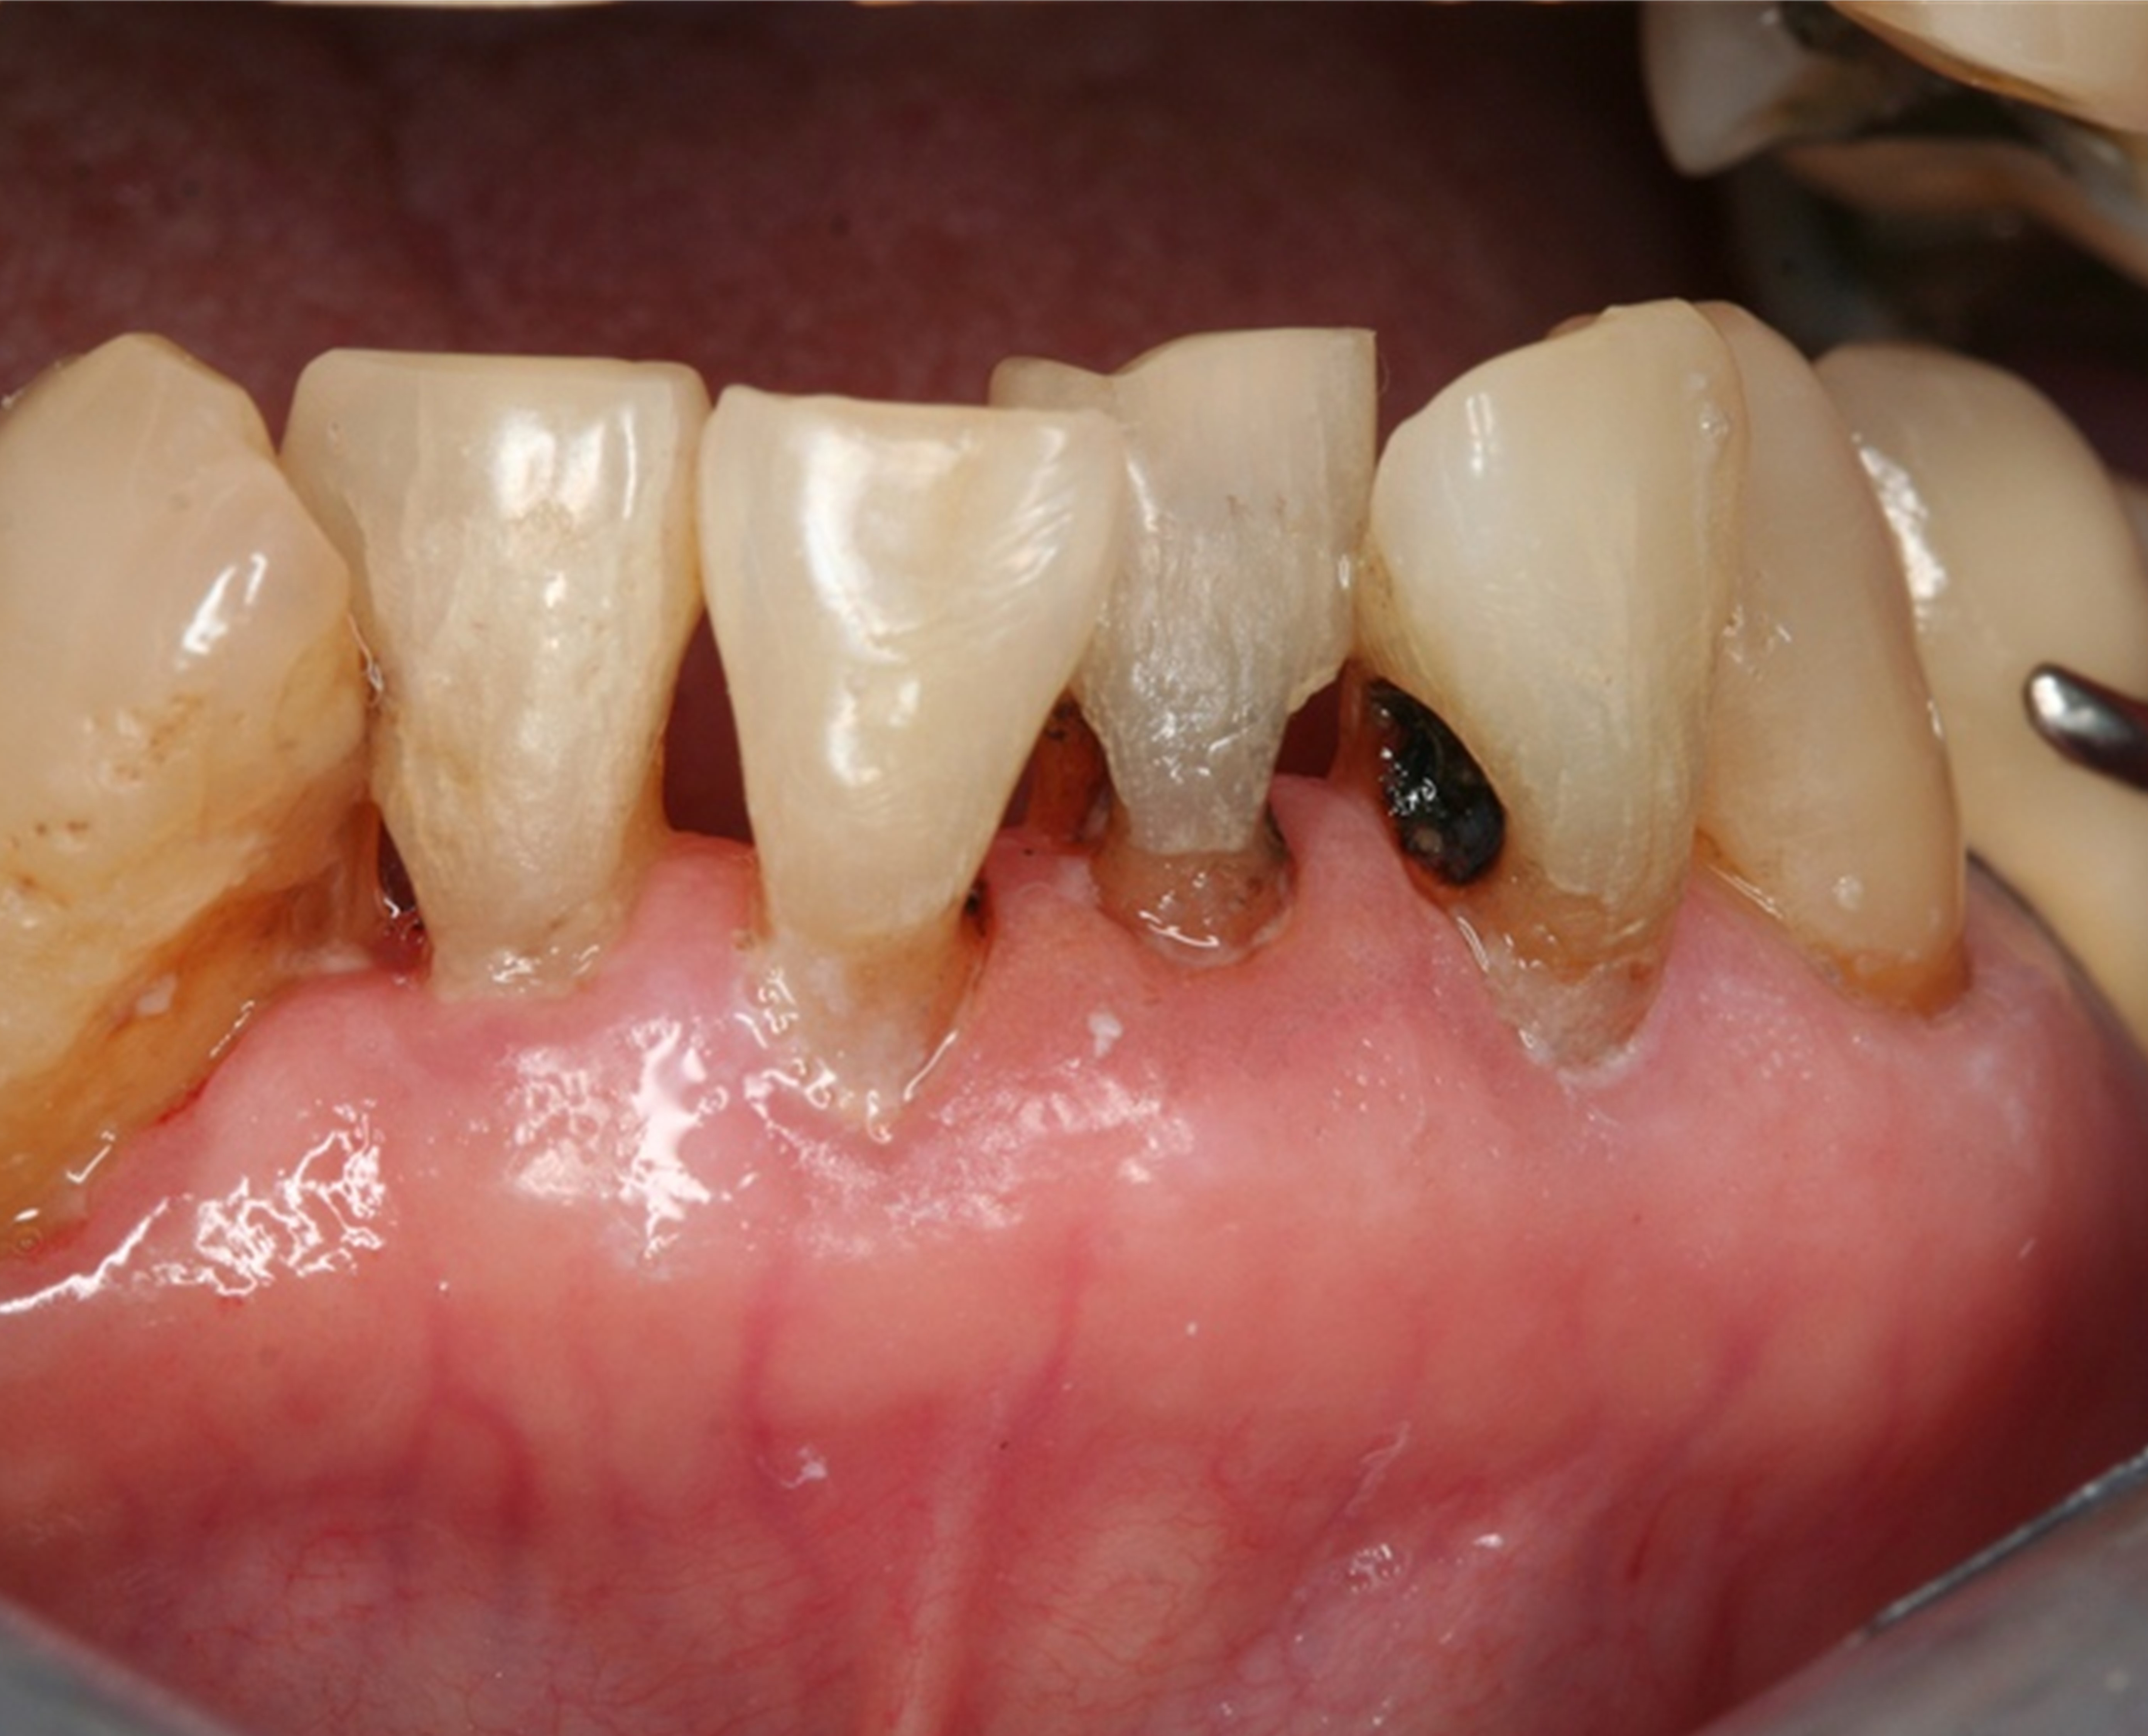

Fig 8. Use of 38% SDF to arrest rampant caries in a young teenager: pre-treatment intraoral frontal view of rampant caries. (image from Chu, et al, 2014, ref 36 [reprinted with approval])

Figure 8

Fig 9. Use of 38% SDF to arrest rampant caries in a young teenager: frontal view of arrested caries after consecutive application of SDF for 3 weeks. (image from Chu, et al, 2014, ref 36 [reprinted with approval])

Figure 9

There is no consensus on the frequency of application, and 38% SDF has been used annually or biannually on clinical trials in children23,31,33,34 and in elderly.30,35 Yee and his co-worker found one-off application of 12% SDF was ineffective in arresting caries in children.31 The present authors applied 38% SDF weekly for 3 weeks to speed up the process of caries arrest and for treatment of rampant caries.36 One of the present authors’ case reports demonstrated that three weekly applications of 38% SDF can arrest rampant caries and relieve pain from hypersensitivity on a teenager. The SDF-treated caries were found arrested, and they turned coal black in appearance (Figure 9).